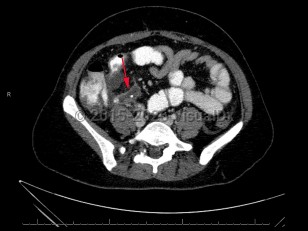

Acute appendicitis is an acute inflammatory condition of the appendix.

Appendicitis results from an obstruction of the appendiceal orifice, which can be caused by a fecalith, lymphoid hyperplasia, infection, calculi, or malignancy. Lymphoid hyperplasia is a more common etiology in younger pediatric patients. Rarely, appendicitis can be caused by infection with the parasitic worm Enterobius vermicularis.

Inflammation begins within the appendiceal lumen and extends through the endothelial wall, leading to focal ischemia, tissue necrosis, and, in some instances, perforation. Perforation can lead to complications including generalized peritonitis and abscess formation.